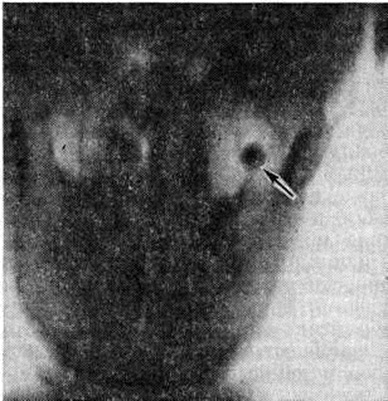

Рис. 2.

Прямая томограмма черепа при остеоме: в левой гайморовой полости видна округлая тень компактной остеомы (указана стрелкой).

Рентгенологические исследование позволяет не только обнаружить Остеома, но и спреде лить её форму, структуру, положение, размеры и взаимоотношение с соседними органами. Компактная Остеома на рентгенограмме имеет форму округло-овальной интенсивной бесструктурной тени (рисунок 2). Губчатая